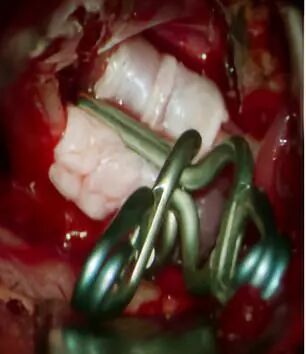

丰育功教授在国内首次提出“鞍区四个解剖间隙”的中文命名,论文《经翼点入路鞍区手术间隙的显微解剖研究》被引用率高达60余次。在国际上首创自体硬脑膜包裹技术结合窗式动脉瘤夹成功处理泡样动脉瘤这一颅内最凶险动脉瘤,取得了非常好的临床疗效,相关成果在SCI杂志Clinical Neurology and Neurosurgery上发表。

于8月18日在全麻下行右侧翼点入路,自体硬脑膜包绕后夹闭,术后康复。